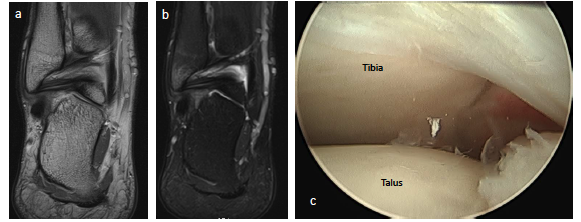

Posterior ankle impingement in athletes is often related to a previous sprain.7,11,12,15,16 Many times, soldiers who sustained syndesmosis injuries can develop a combination of soft tissue impingement lesions not only anteriorly but posteriorly as well (see first photo set above). We also see clicking, popping and snapping of the posterior tibiofibular ligament and posterior talofibular ligament in these cases. In a sense, we can see a posterior pseudo-version of Bassett’s ligament although this is not named as such. Whether this is a fraying of the ligament which now impinges on the posterior tibial lip or a true accessory ligament is not well-defined. Regardless, the imaging is often clear on MRI and intra-operatively (see second image set above). Almost every author states that symptoms always or only occur with plantarflexion, but I tend to see far more soldiers and athletes complaining of pain with dorsiflexion. To me, pain with stretching of the posterior capsule and distraction of the offending tissue makes far more sense that hurting with only plantarflexion.

Once I am in the posterior space I can inspect the ankle laterally and centrally. Simply dorsiflexing the ankle widens the space. By switching the scope to the medial portal, you can inspect the medial joint and easily visualize the deep deltoid ligament. Just like one would do with the anterior ankle, surgeons can divide the joint into medial, central and lateral quadrants (see fourth photo set above). Once the surgeon is done with the ankle joint, proceed inferiorly to inspect the posterior talar process/os trigonum and, if necessary, the posterior facet (see fifth photo set above).